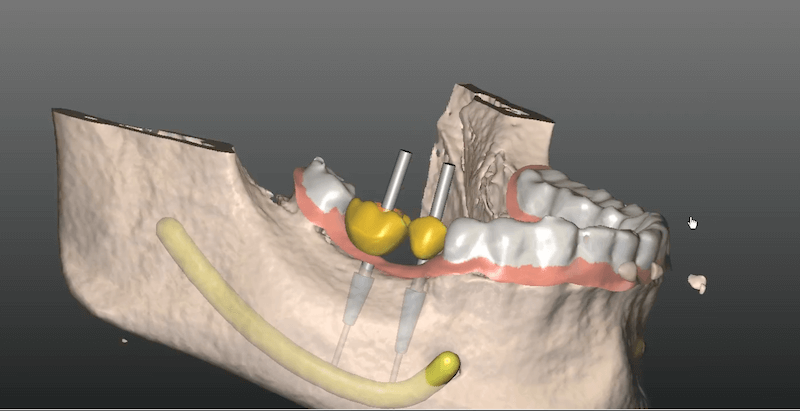

Ezután a CT felvételt és a CBCT sablonról készült felvételt beolvassuk a SMART Guide tervező szoftverébe. Így láthatóvá válik a rendelkezésre álló csontszövet minősége és mennyisége valamint az idegcsatornák és az arcüregek elhelyezkedése is. Ez alapján kiemelkedő pontossággal tudjuk megtervezni az implantátum elhelyezkedését és méretét.

Az elkészült műtéti terv alapján 3D nyomtatással készíttetünk egy egyedi, kizárólag az adott páciens szájüregébe illeszkedő műtéti segédeszközt, az implantációs sebészi sablont. Ez a sablon gyakorlatilag egy átlátszó, szájba helyezhető műanyag fogmodell fémbetétes lyukakkal. A lyukak tökéletesen vezetik a fúrósorozatot, így a furatok egészen biztosan az előre megtervezett helyre fognak kerülni. További előny, hogy a sablon alapján jóval kisebb bemetszést kell ejteni, így gyorsabb gyógyulás érhető el.

A SMART Guide digitális navigációs rendszer mérnökök, orvosok és fogtechnikusok közös fejlesztése, melyett hosszú ideig teszteltek. További pozitívum, hogy nem kötődik egyetlen implantátum márkához sem, így bármely implantátum-típus esetén sikeresen alkalmazható. Ssegítségével a kiterjedt foghiányok is hatékonyan kezelhetőek, mivel a rendszer több implantátum behelyezésénél is jelentősen növeli a beavatkozás térbeli pontosságát.